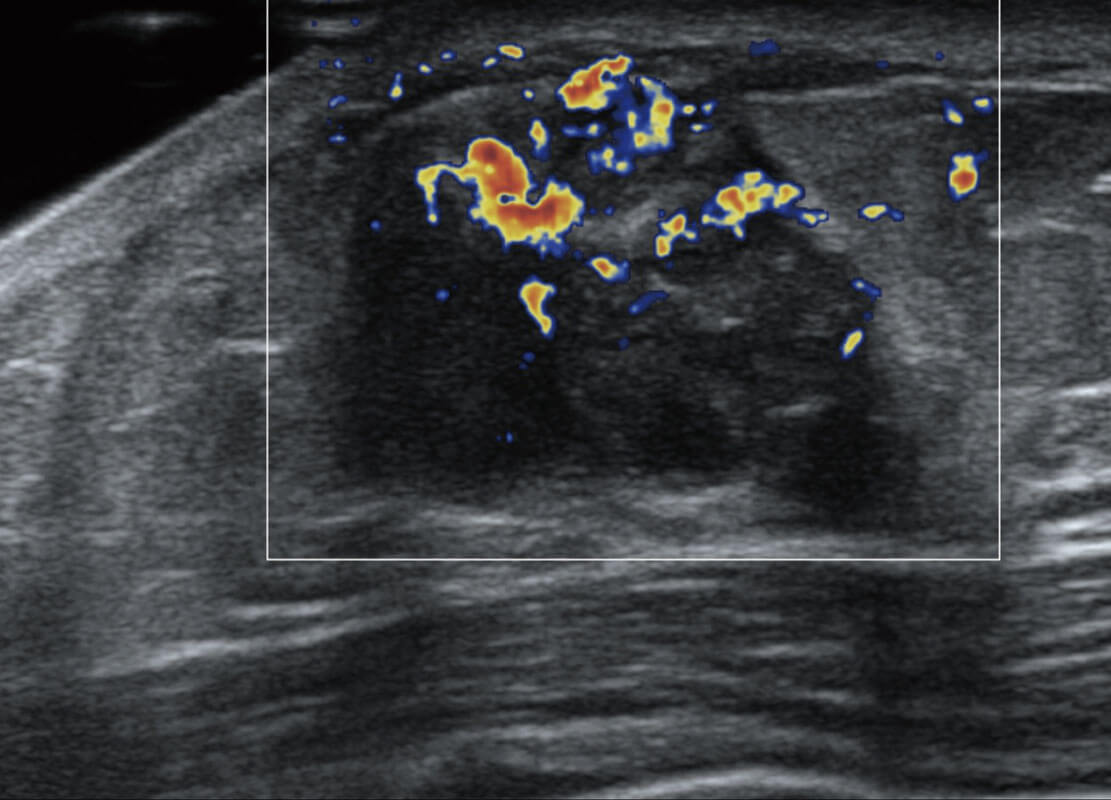

P60搭載寬頻帶線陣探頭、寬景成像、彈性成像技術(shù),為您提供乳腺應(yīng)用方案。P60支持高頻相控陣探頭、線陣探頭、腹部高頻探頭、腹部微凸探頭等,豐富的探頭群搭載敏感的彩色血流成像,適用于新生兒多種臟器檢測要求,滿足新生兒篩查需求。

新生兒肝血管癌